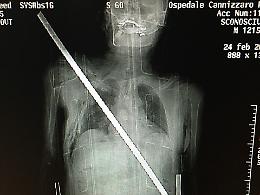

«Io, trafitto da una barra di ferro salvato dagli "angeli" del Cannizzaro»

CATANIA - Si sente un miracolato, dopo essere volato giù dal tetto di un ...

21.03.2017